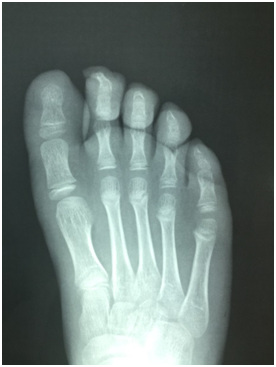

The locations ordered by frequency were, two cases (50 %) in the fourth finger, one case (25 %) in the second finger (Figures 1 & 2) and one case (25 %) in first finger, all of them in the distal phalange (Figures 3 & 4). Right foot was more frequent with 3 cases, compared to only one case on the left foot. Only one patient performed a surgical intervention for symptomatology and development maturation. Only one patient underwent surgery to improve pain and demostrate adequate development of epiphyseal plaque.

Figure 1 Subungual osteochondroma in the second distal phalanx.

Figure 2 Dorsoplantar X-ray projection it´s observed a pedunculated expansion of trabecular bone from the epiphyseal region of the second distal phalanx.